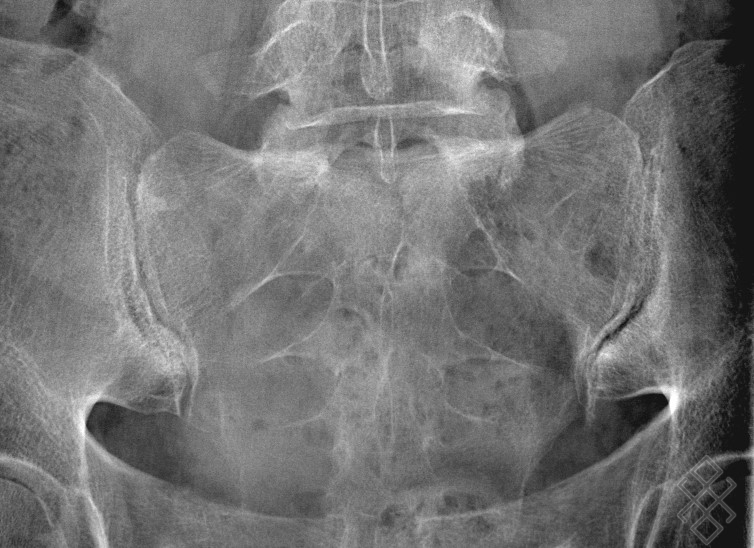

Source: mehliuslam.pages.dev LA DOULEUR SACROILIAQUE ET OU HERNIE DISCALE (SCIATIQUE) Sicotte DC , The evaluation of the sacroiliac joints begins with conventional radiography (24, 28, 40) - Schéma de l'orientation des articulations sacro-iliaques et matérialisation du rayon incident

Source: waffcodli.pages.dev PPT Prise en charge du patient Polytraumatisé PowerPoint Presentation ID5492953 , The evaluation of the sacroiliac joints begins with conventional radiography (24, 28, 40) Connaître les différentes pathologies rencontrées et la place de l'imagerie dans l'apport…

Source: fieldfiticr.pages.dev Radiographie des Sacroiliaques Définition & Déroulement Prise de rdv en ligne , Case study, Radiopaedia.org (Accessed on 22 Mar 2025) https://doi.org/10.53347/rID-30253 The wide variations in interpreting radiographs of the sacroiliac spine (41, 54, 103), both in the same observer and between different observers, have made it necessary to add other imaging examinations.